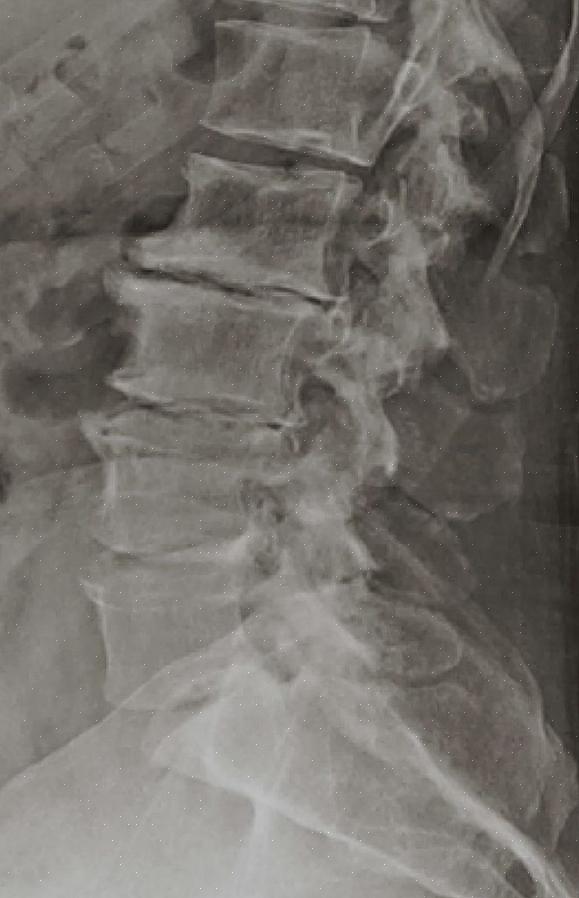

דיסק חולייתי הוא חלק מעמוד השדרה. הם מבנים רכים היושבים בין החוליות כדי לספק גמישות ולפעול כבולמי זעזועים. יש להם מרכז רך וחלק חיצוני קשה יותר.

למרות שכל חלק בעמוד השדרה יכול להיות מושפע ממחלת דיסק ניוונית, זה נפוץ יותר באזורי צוואר הרחם והמותניים. דיסקים החולייתיים בחתך בית החזה סובלים מבעיה זו לעיתים רחוקות.

ניוון הדיסק הוא למעשה לא בעצמו הגורם לתסמינים. הבעיה היא שדיסקים מתנוונים מתכווצים ומשנים צורה; זה משנה את סידור החוליות.

אחת ההשלכות היא דלקת מפרקים ניוונית, שבה החוליות באות במגע אחת עם השנייה והופכות מרותכות. תוצאה נוספת היא פריצת דיסק, שבה חלק מהדיסק בולט מחוץ לציר עמוד השדרה ויכול לסחוט עצבים.

לבסוף, יש גרסה של פריצת הדיסק הנקראת היצרות תעלת השדרה. זה המקום שבו הדיסק בולט פנימה במקום החוצה.